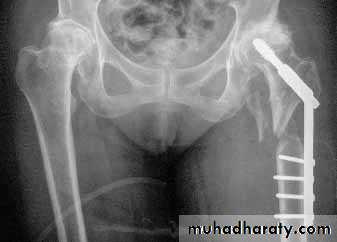

3.Treatment depend on the type and age of the patient

4.DHS.

1.Sliding nail

2.L-plate